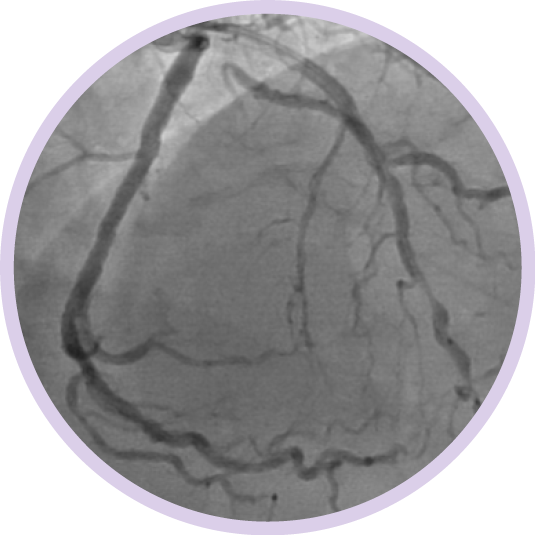

Ангиография дает сведения о характеристиках просвета сосуда, но не позволяет получить четкого изображения сосуда и поражения.

Между тем, использование ВСУЗИ помогает получить более четкую картину и улучшить результаты лечения пациента за счет планирования стентирования на основе данных и оптимизации стента после его установки1.